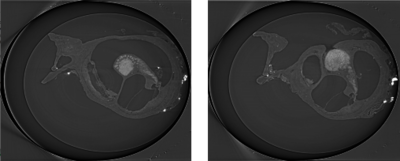

Sensorineural hearing loss, which is the most common type of hearing impairment, originates from damaged inner ear nerves. However, this can be treated in many cases by regenerating the synaptic connections between the extant Spiral Ganglion Neurons (SGNs) and transplanted human stem ... Read More